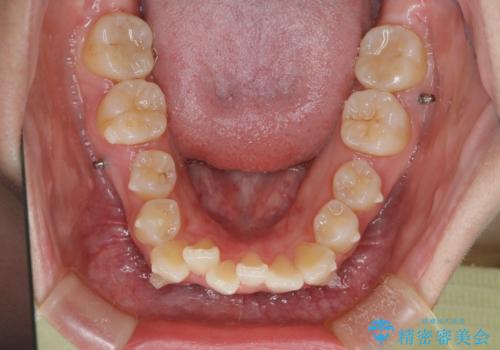

【インビザライン】前歯の凸凹を非抜歯で治療

- 前歯の凸凹を主訴の来院されました。

奥歯を後ろの方に移動させるために矯正用のアンカースクリューを使いながら治療をおこないました。

患者さんの都合により、マウスピースの装着時間が不足したため、途中からワイヤーにて治療を行いました。